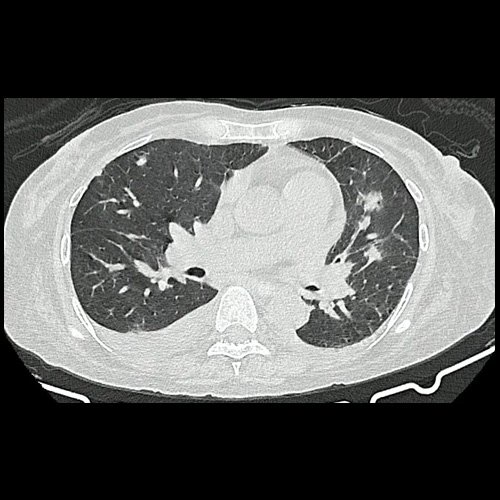

• TAC tórax (un mes atrás):La porción visualizada de la glándula tiroides es de características normales. Las estructuras vasculares paraaórticas son de características normales, permeables. La aorta ascendente, el cayado y la aorta descendente son de calibre y trayectoria conservados. Las estructuras venosas mediastinales: vena cava superior, vena cava inferior, venas pulmonares superiores e inferiores y venas ácigo-hemiácigos, son de calibre y trayecto conservado. La arteria pulmonar y sus ramas son de calibre y trayecto conservados.. Relación aórtico-pulmonar conservada. El corazón es de tamaño normal. El pericardio es de espesor conservado. El esófago es de calibre y trayecto normales. El mediastino está en posición central. Estructuras ganglionares pre y laterotraqueales, subcarinales, axilares bilaterales, aumentadas en número y de tamaño, algunas de ellas de rango megálico, destacándose una axilar izquierda con pérdida de la morfología habitual que mide 10 mm en su eje corto.

• TAC de tórax sin contraste - informe preeliminar (Dia 31):  Estudio artefactado por movimientos respiratorios de la paciente. Se observan múltiples lesiones nodulares sólidas, irregulares, heterogéneas, que se extienden por ambos campos pulmonares a predominio derecho, de manera periférica y subpleurales, asociadas a vidrio esmerilado, destacándose la de mayor tamaño en segmento lingular inferior que mide 12 mm x 16mm. Hallazgos que podrían corresponder en primera instancia a proceso inflamatorio infeccioso sin poder descartar secundarismo. Se sugiere control evolutivo.  Hallazgos no visualizados en Tc del día 05-08-2025, si se observan en TC del día 24-09-2025. Bulla subpleural paramediastinal, de 14mm, en segmento posterior del LSI. Leve derrame pleural, en esta ocasión, bilateral, de mayor jerarquía a derecha. Múltiples estructuras ganglionares pre y lateroaórticas, axilares bilaterales aumentada en número y de tamaño, de rango no megálico. Laminar derrame pericárdico.

TAC de tórax (internación previa)

TAC de tórax (Dia 31)